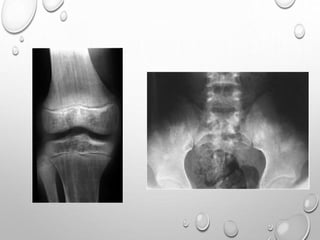

EPIPHYSEAL DYSPLASIA

MULTIPLEX

AD TRANSMISSION

EQUAL IN MALES AND FEMALES

FIRST NOTICED WHEN CHILD BEGINS TO WALK , WITH COMMON

COMPLAINTS OF WADDLING GAIT , DIFFICULTY RUNNING.

MILDER CASES MAY NOT APPARENT UNTIL EARLY ADULTHOOD ,

WHEN PREMATURE JOINT DEGENERATIVE CHANGES OCCURS.

PATHOPHYSIOLOGY : ABNORMALITY OF EPIPHYSEAL

CHONDROCYTES ( NO DECREASED , ABNORMAL ARRANGEMENT

)….LEADING TO DELAYED AND DISORDERLY OSSIFICATION F

EPIPHYSES.

LL >> UL

SHORT STATURE WITH TENDENCY TOWARDS DWARFISM

BILATERAL SYMMETRICAL INVOLVEMENT

DEVELOPMENT OF EPIPHYSES DELAYED

APPEARANCE IS MOTTLED WITH IRREGULAR MINERALIZATION

FLATTENED AND SQUARED-OFF EPIPHYSES

DOUBLE LAYERED PATELLA……PATHOGNMONIC

HYPOPLASTIC TIBIAL AND FEMORAL CONDYLES WITH SHALLOW

INTERCONDYLAR NOTCH

METAPHYSES ARE FLARED

CARPALS , TARSALS AND LONG TUBULAR BONES OF HAND ,SOMETIMES

FEET ARE SHORT AND THICK

SPINE : ANTERIOR WEDGING , SCOLIOSIS

IRREGULAR EPIPHYSES LEADS TO PREMATURE AND SEVERE

DEGENERATIVE CHANGE ESPECIALLY IN KNEES AND HIPS.

PELVIS

SMALL

ILIA ARE SHORT CAUDALLY

HORIZONTALLY PLACED ACETABULLA , THICKENED Y CARTILAGE

LIMBS

UL> LL

RHIZOMELIC TYPE

METAPHYSIS …..SPLAYING , CUPPING

GENU VERUM

TRIDENT HAND

TIBIA , ULNA ARE MORE SHORTENED THAN FIBULA , RADIUS

V SHAPED NOTCH IN GROWTH PLATE

SHORT , TUBULAR LONG BONES OF HAND AND FEET

FINGERS ARE OF SAME LENGTH

MENTAL AND SEXUAL DEVELOPMENT ARE NORMAL